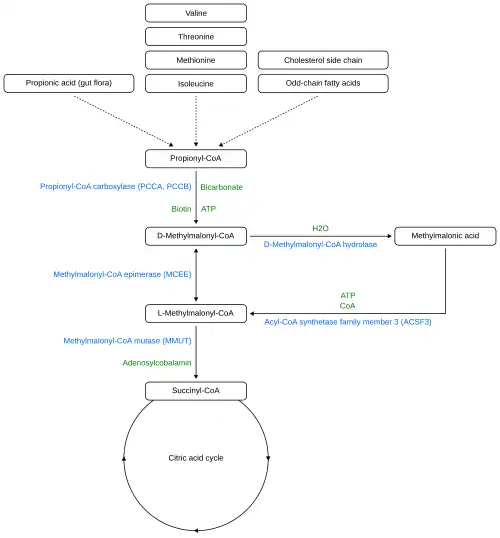

Vitamin B12 deficiency causes particular changes to the metabolism of two clinically relevant substances in humans:

- Homocysteine (homocysteine to methionine, catalysed by methionine synthase) leading to hyperhomocysteinemia

- Methylmalonic acid (methylmalonyl-CoA to succinyl-CoA, of which methylmalonyl-CoA is made from methylmalonic acid in a preceding reaction)

Methionine is activated to S-adenosyl methionine, which aids in purine and thymidine synthesis, myelin production, protein/neurotransmitters/fatty acid/phospholipid production and DNA methylation. 5-methyl tetrahydrofolate provides a methyl group, which is released to the reaction with homocysteine, resulting in methionine. This reaction requires cobalamin as a cofactor. The creation of 5-methyl tetrahydrofolate is an irreversible reaction. If B12 is absent, the forward reaction of homocysteine to methionine does not occur, homocysteine concentrations increase, and the replenishment of tetrahydrofolate stops.[137] Because B12 and folate are involved in the metabolism of homocysteine, hyperhomocysteinuria is a non-specific marker of deficiency. Methylmalonic acid is used as a test of B12 deficiency, but has a low specificity.